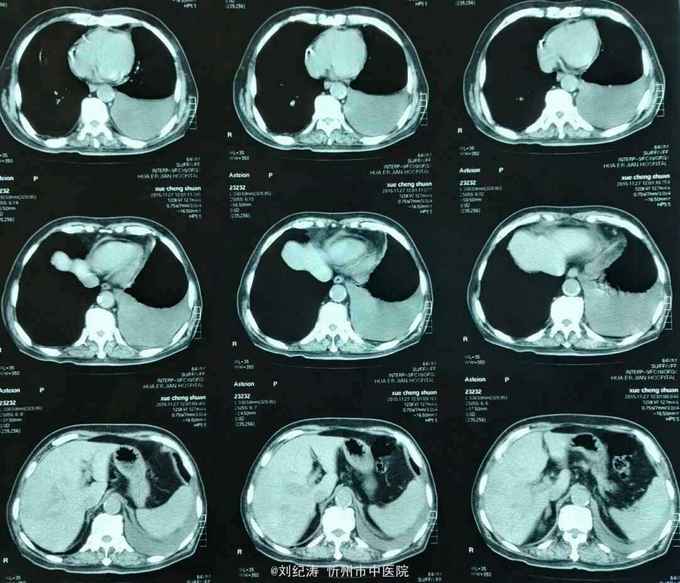

查体:ECOG评分:3分,生命指征平稳,浅表淋巴结未触及明显肿大,双眼睑无水肿,唇无发绀,颈软,双侧胸廓对称,左肺语颤增强,左肺呼吸音消失,右肺呼吸音粗,可闻及哮鸣音,心律齐,腹平软,肝脾肋下未触及,移动性浊音阴性,肠鸣音3次/分,双下肢无水肿。 辅助检查:血常规(2016.1.1):WBC:10.6*109/L,RBC:4.69*1012/L, PLT:165*109/L ,HGB:167g/L.生化(2016.1.1):谷丙转氨酶11U/L,谷草转氨酶11U/L,总蛋白60g/L,白蛋白33g/L,尿素:9.8mmol/L,肌酐:123umol/L,尿酸:251 umol/L,血糖:7.37 mmol/L;电解质:钾:4.79mmol/L,钠:123.5 mmol/L,氯:85.7 mmol/L,钙:2.03 mmol/L。肺部CT(2016.1.1):左肺完全萎缩,左侧胸腔大量积液,右肺未见异常,纵膈轻度右移,未见明显肿大淋巴结。

诊断: 1.左肺癌 左侧胸腔积液 左肺不张;2.2型糖尿病;3.低钠、低氯血症;4.低蛋白血症 治疗 完善检查,予以胸腔穿刺置管引流胸水以减轻心肺负荷,静脉给予抗感染、祛痰、止咳、平喘、提高免疫、扶正抑瘤、营养支持、调节电解质平衡及对症治疗。